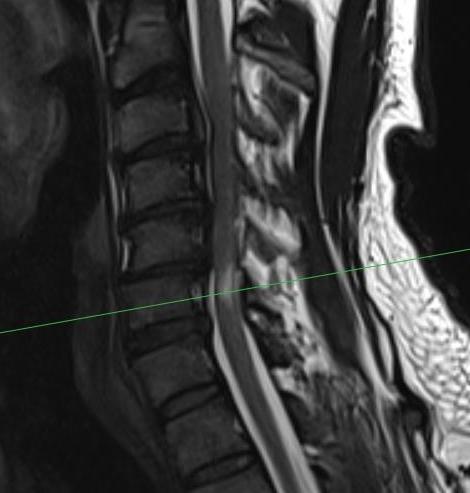

MRI

Stenosis

Cord injury

- high signal intensity on T2

- localise level of injury